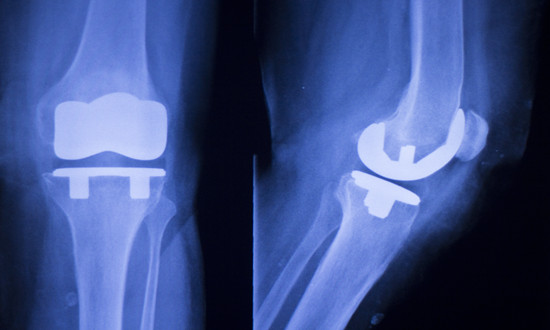

骨科植入器材是指被植入人体内,用于取代、修复、补充、填充或辅助治疗受损伤骨骼的器材的统称。它们主要由金属材料、生物陶瓷材料、高分子材料等制成,可以长期植入人体,对人体的生命和健康有着重大影响。骨科植入......

骨科植入医疗器械,指的是通过手术植入人体,可以起到替代、支撑人体骨骼或者可以定位修复骨骼、关节、软骨等组织的器材材料,主要包括骨接合植入物及关节植入物,如接骨板、接骨螺钉、髓内钉、脊柱内固定植入物、人......